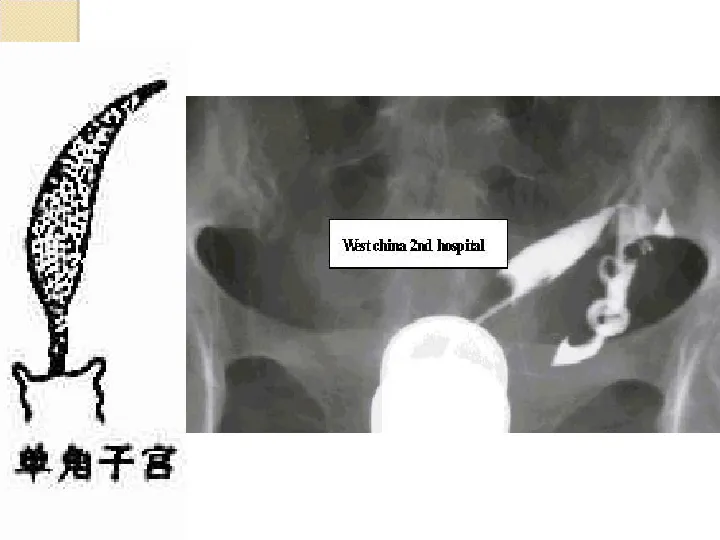

>【影像PPT】子宫输卵管造影

【影像PPT】子宫输卵管造影